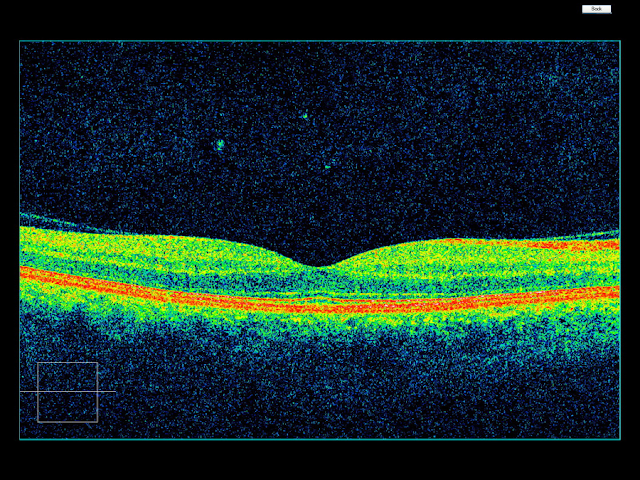

| Fig. 1 Presentación de una imagen del OCT |

El propósito del OCT, es detectar anormalidades en la retina (Fig. 2) en términos de espesor, morfología y reflectividad. La determinación del diagnóstico es el resultado de un proceso de:

Es así como el OCT (Fig. 3) al igual que toda disciplina posee términos propios para poder describir de manera cualitativa y cuantitativa los resultados del examen, de manera que se pueda interpretar y describir una patología sin tener que decir el nombre es esta.

Para empezar a describir un examen de OCT (Fig. 24), es preciso conocer el siguiente orden de estructuras:

| Fig. 24 Orden de descripción de una imagen de OCT |